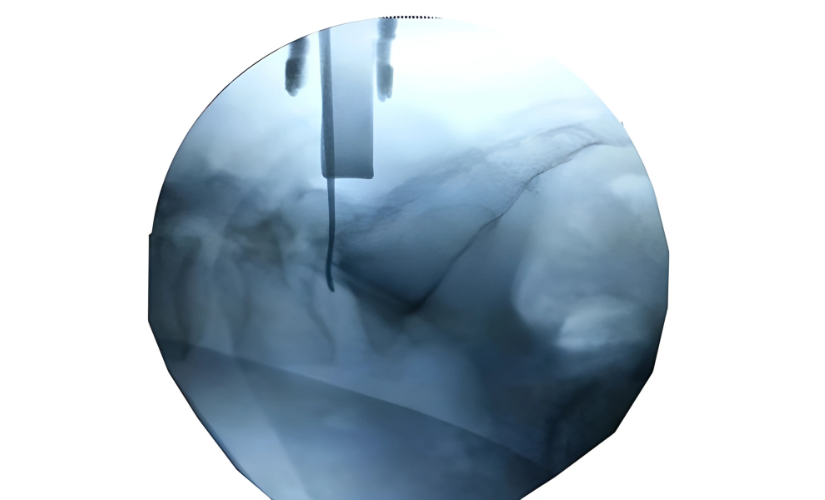

Traditional surgery to access the pituitary gland required a craniotomy (opening the skull). However, with the advancement of endoscopic transnasal surgery, this procedure can now be performed through the natural nasal passage — avoiding any external incisions.

Once diagnosed, Dr. Rahul Gupta and his multidisciplinary team — including endocrinologists and neuro-ophthalmologists — create a personalized treatment plan. For most pituitary tumors, endoscopic transnasal surgery is the gold-standard approach. Through one of the nostrils, a thin endoscope equipped with a high-definition camera provides a magnified view of the tumor area. Using specialized microsurgical instruments, the tumor is carefully removed through this corridor without disturbing surrounding brain tissue.

This technique allows for excellent tumor clearance while minimizing trauma. In some cases, where the tumor is very large or extends into the cavernous sinus, a staged or combined approach may be used. If the tumor produces excess hormones, medical therapy may be prescribed post-surgery to stabilize hormonal balance.